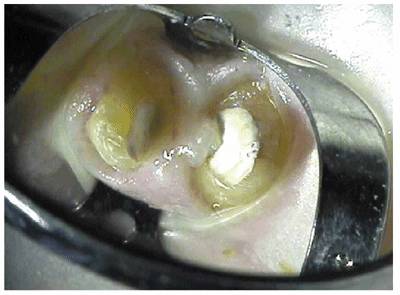

A carefully planned and executed access cavity preparation should minimize

weakening the tooth, provide for maximum visibility, and allow for straight

line access into all root canals for optimal preparation and filling of the

canal(s) (Figure 19-44

Figure 19-44: Straight line access allowed for visualization of all four canals in the maxillary second molar.

Morphologically, the access cavity takes the shape of the underlying pulp

chamber (Figures 19-45A

to C).